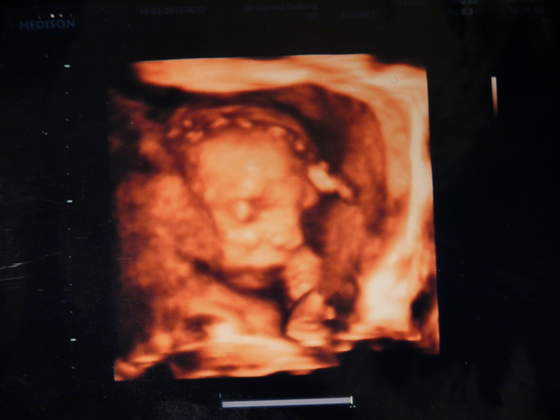

a oto mój synek w połowie drogi :-) (22 tydzień)

może trochę nie wyraźne - ale ja tam widze podobieństwo do męża hihihi